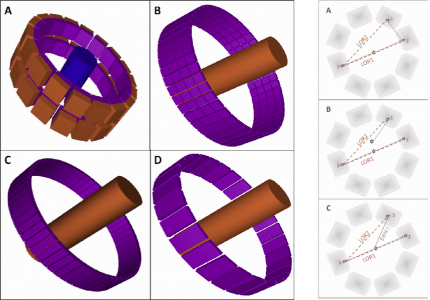

| ABSTRACT | When multiple pinholes are used to acquire SPECT projection data, there may be regions on the detectors where data from two or more pinholes overlap. Such “multiplexing” of projection data can cause artifacts and/or increased noise in reconstructed SPECT images, depending on the exact acquisition geometry. We previously described a modified MLEM algorithm that alternates between (i) estimating the separated projection data that would be obtained through each individual pinhole (i.e., demultiplexed data), based on the current MLEM iteration’s image, and (ii) reconstructing the SPECT image by MLEM, but assuming that the demultiplexed data estimates are the actual measured data. The modified MLEM algorithm was first tested with data simulated for a stationary 39pinhole collimator tube, and more recently with Tc99m phantom data acquired from three vials of different sizes on a 6pinhole, tripledetector SPECT camera. |